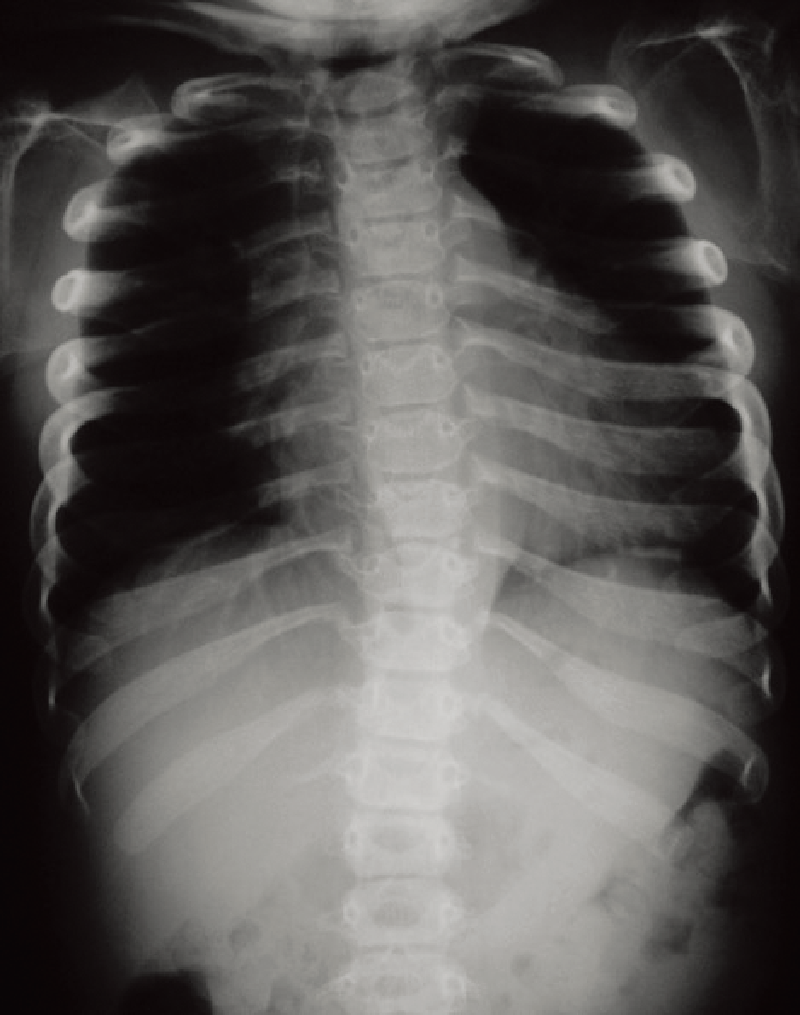

A. 全脊柱正面像(11歳、女):著明な脊柱側弯を認める。